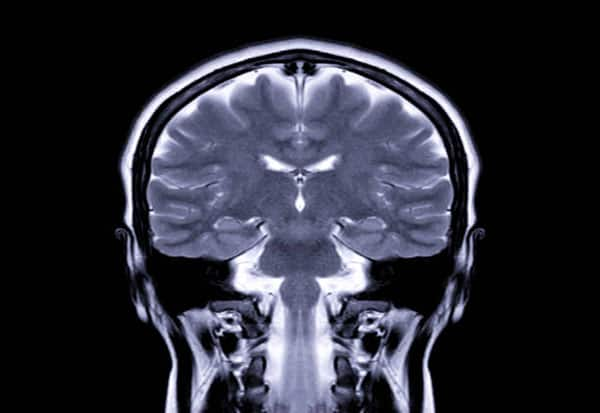

New Delhi: Brain processes involved in learning may naturally fluctuate in line with the female reproductive cycle and be linked with molecular changes driven by dopamine production, according to a new study in mice, findings from which could help explain how the neurochemical aids learning in humans.

Researchers found that learning abilities in mice improved when oestrogen levels were increased, likely because the hormone boosts dopamine activity in the brain's reward centre, strengthening reward signals. When oestrogen activity was suppressed, dopamine regulation weakened, leading to reduced learning.